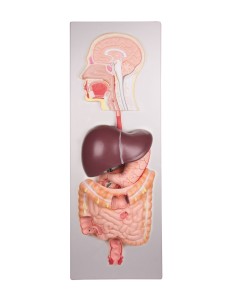

Dal cranio in 22 parti con incastri magnetici ai modelli di colonna vertebrale, da quelli di articolazioni a quelli di cuore, ogni pezzo della nostra collezione è progettato per un’immersione totale nello studio dell’anatomia umana. I nostri modelli, realizzati tramite scansioni di ossa vere, garantiscono un’esperienza tattile autentica e una fedeltà di peso quasi identica agli originali.

Essenziali per studenti e professionisti, i nostri modelli anatomici sono strumenti didattici che permettono di osservare le strutture anatomiche con precisione, eliminando la necessità di dissezioni o studi invasivi. Sono inoltre utili per spiegare ai pazienti le patologie, rendendo la comunicazione più efficace e risparmiando tempo prezioso.